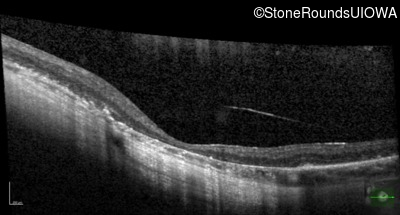

Age at visit: 15 years

OD OS

This 15 year old male had a macular abnormality noted two weeks ago when he was refracted for his first pair of glasses. Bone spicule-like pigmentation was first noticed a year later (age 16) during a routine follow-up eye exam.